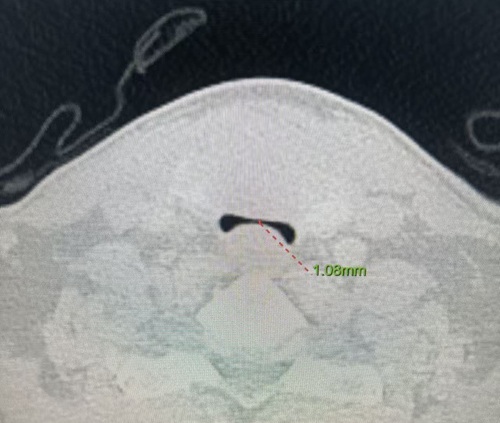

患者薛伯伯罹患甲状腺乳头状癌,肿瘤不仅侵犯被膜及周围结缔组织,更严重压迫气管,导致气管变形。CT提示气管受压显著,随时可能发生气管塌陷或术中大出血,引发窒息风险。此类病情常涉及气管切除重建、神经保护、术后气管插管及ICU监护等多重挑战。

图1术中狭窄的气管;图2术前气管影像;图3术后气管影像